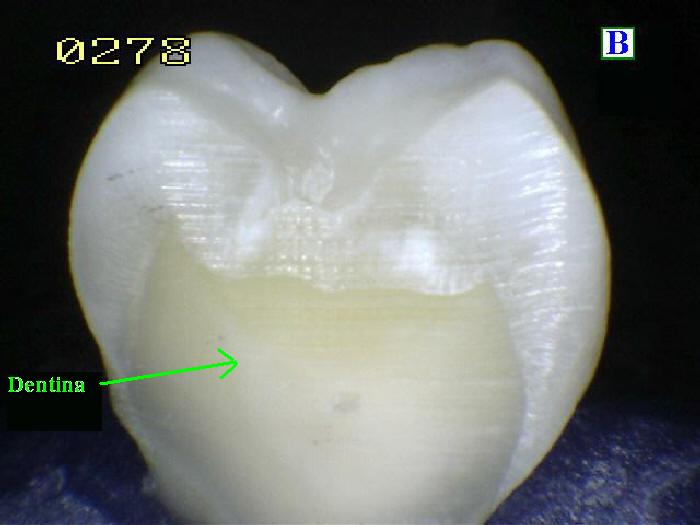

La

Dentina es la sustancia entre

el esmalte o cemento y la cámara pulpar. Es

secretada por los odontoblastos de la pulpa

dental. [13] La formación de dentina se conoce

como dentinogénesis. El material poroso de color

amarillo está compuesto por 70% de materiales

inorgánicos, 20% de materiales orgánicos y 10%

de agua en peso. [14] Debido a que es más suave

que el esmalte, se descompone más rápidamente y

está sujeto a caries severas si no se trata

adecuadamente, pero la dentina aún actúa como

una capa protectora y sostiene la corona del

diente.